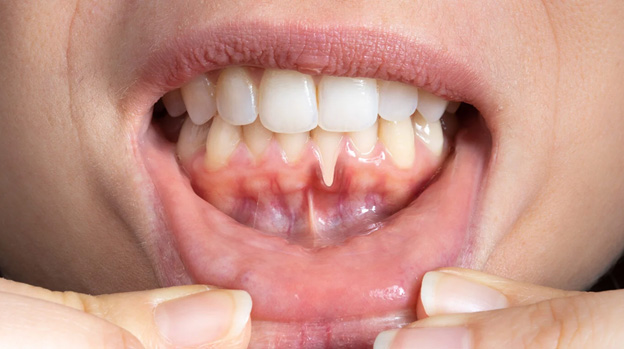

Gum recession is a common dental problem where the gum tissue pulls away from the teeth, exposing the roots. This can lead to tooth sensitivity, increased risk of decay, and even tooth loss if left untreated.

Gum recession denotes gum disease where the gum tissue withdraws from the teeth, uncovering the roots beneath. It increases the susceptibility of teeth to cavities and can lead to heightened tooth sensitivity during brushing and eating. One or multiple teeth may be involved. While gum recession can impact individuals of all age groups, it is more common in people over 65.

Bleeding Gums: Gums might bleed during brushing or flossing.